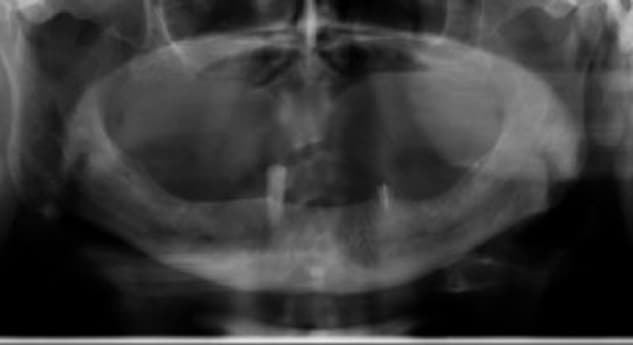

Case Summary: A patient presented with a dental implant exhibiting severe inflammatory environment. The condition had advanced to the point where the implant was considered non-salvageable and scheduled for extraction. Dr. Eli Raviv prior to using the MED removed a neighboring implant due to a similar condition, reinforcing the severity and hopeless prognosis of the current case.

Treatment Approach: Instead of proceeding with immediate removal, Dr. Raviv opted for a treatment using Magdent's MED healing abutment. The first MED was placed for a continuous 30-day period and a second MED for another 30-days period, delivering localized Pulsed Electromagnetic Field (PEMF).

Clinical Outcome:

• Pocket Depth: Reduced to 2mm-clinically healthy tissue level.

• Follow-Up: At the 1-year mark, the implant remained stable and functional, with no signs of active inflammation or bone loss.

Inflammatory environment Regeneration (Dr. Eli Raviv, Associate Professor, McGill University). A patient presented with severe inflammatory environment, showing a probing depth of 6 mm and advanced bone loss. The implant was initially considered non-salvageable and scheduled for extraction, especially as an adjacent implant had previously been removed due to the same condition. The case represented a critical-stage peri-implant infection, typically associated with poor prognosis and progressive bone destruction.

Instead of proceeding with implant removal, Dr. Eli Raviv implemented a regenerative, non-surgical treatment protocol using the Magdent MED healing abutment. The first MED device was placed for 30 consecutive days, delivering localized Pulsed Electromagnetic Field (PEMF) stimulation directly to the peri-implant site. After completion of the first cycle, a second MED was installed for an additional 30 days to extend the stimulation period and maximize regenerative outcomes. Throughout the treatment, no additional surgical intervention was performed.

• Within weeks, the site showed marked improvement in soft tissue tone and reduction of inflammation.

• At 1 year, clinical measurements revealed a reduction of pocket depth from 6 mm to 2 mm—representing a 200% improvement in clinical attachment level and return to healthy peri-implant conditions.

• At 15 months follow-up, the implant remained fully functional and stable, with no bleeding on probing, no radiographic bone loss, and complete resolution of the previous inflammatory lesion.

• This case demonstrates the potential of MED-based PEMF therapy to reverse severe inflammatory environment in cases once deemed unsalvageable, providing a non-invasive, regenerative alternative that restores implant stability, bone integrity, and long-term peri-implant health.